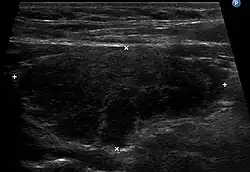

Sehr wichtig für die Diagnose ist zudem ein Sonogramm der Schilddrüse. Typischerweise erscheint die Schilddrüse im Ultraschallbild inhomogen und echoarm, was auf die laufende Zerstörung hinweist. Zudem kann die im Doppler-Sonogramm erkennbare verstärkte Durchblutung ein Hinweis auf eine Entzündung sein. Auch die Größe der Schilddrüse kann im Sonogramm beurteilt werden. Da die hypertrophe Form der Hashimoto-Thyreoiditis mit einer Struma einhergehen kann, sind Größen über ca. 18 ml (Frauen) bzw. ca. 25 ml (Männer) Gesamtvolumen als auffällig anzusehen. Kleine Schilddrüsen mit einer Größe unter 6 ml (Frauen) bzw. 8 ml (Männer) sind hingegen typisch für die atrophische Verlaufsform (Ord-Thyreoiditis), wobei einschränkend angemerkt werden muss, dass diese Größenangaben – je nach Autor – stark schwanken und Gegenstand der Diskussion sind. In Deutschland ist die sogenannte atrophische Verlaufsform mit schrumpfender Schilddrüse weitaus häufiger als die hypertrophe Form mit Kropfbildung (Struma).

- Mögliche Diagnose: Hypoechogene und/oder inhomogene Struktur in der Schilddrüsensonographie